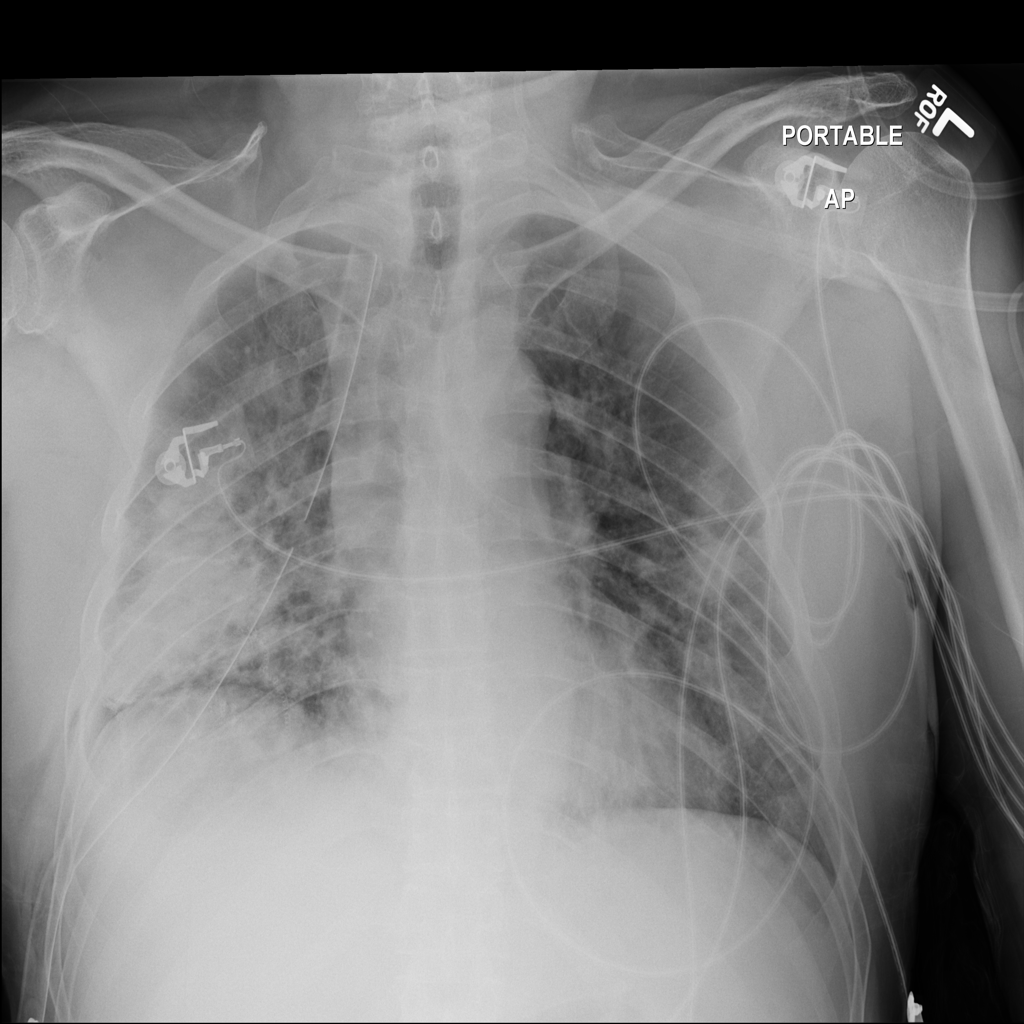

PAT-A380 · IMG-002Consolidation

PAT-A380 · IMG-002

AP